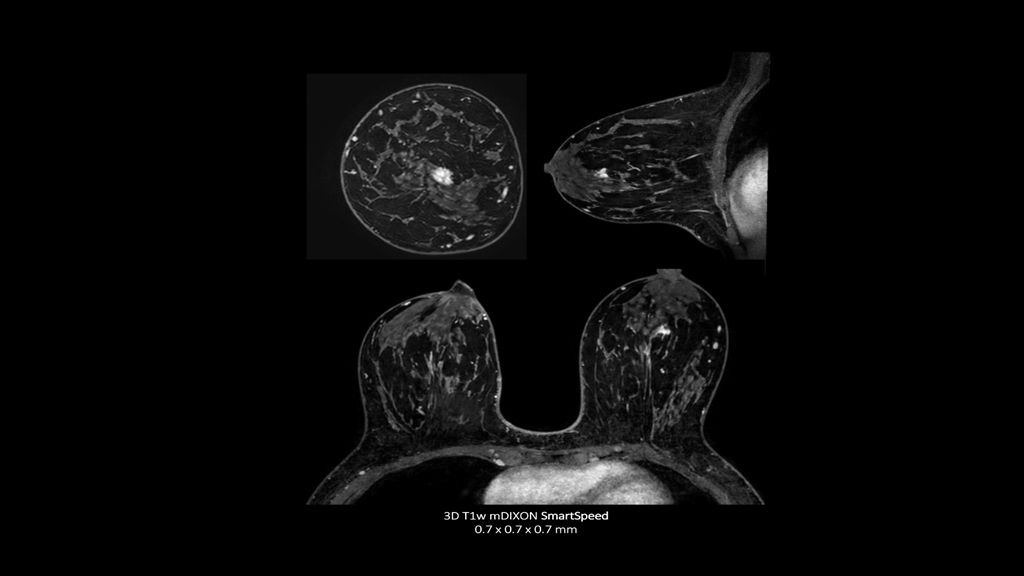

Philips - SmartSpeed Precise- Breast NMRF445C - Philips